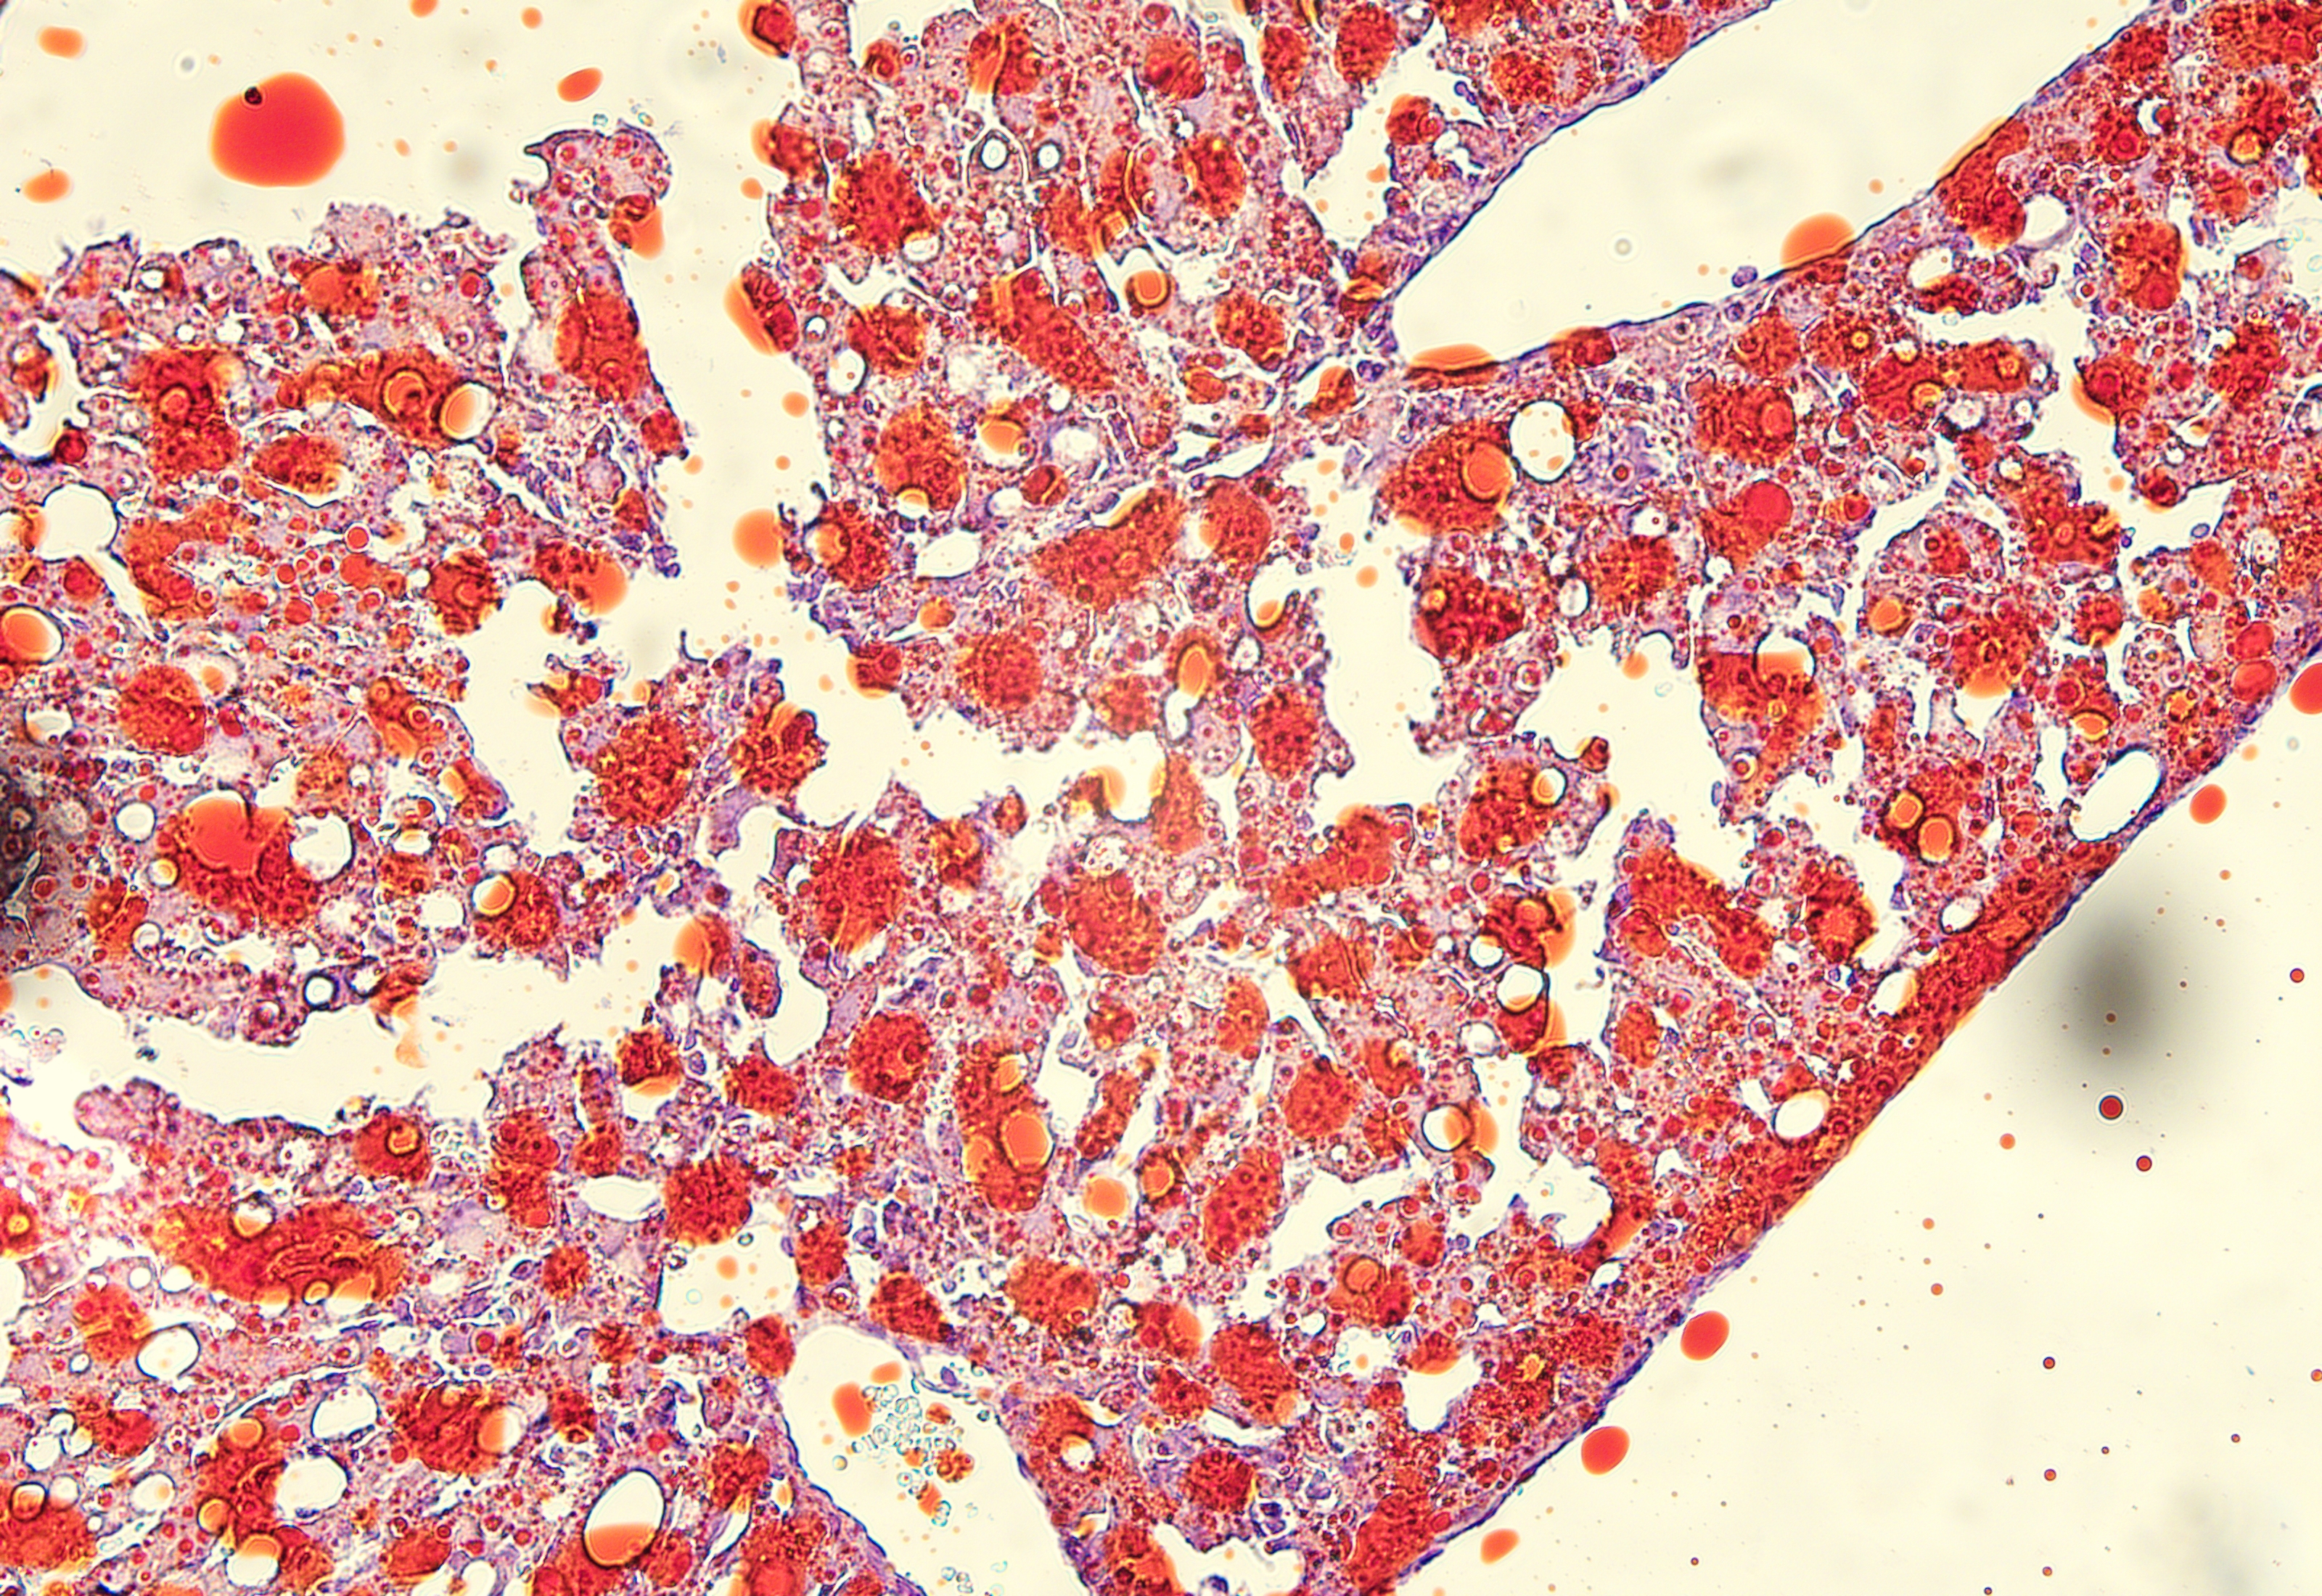

油红O染色

脂肪肝模型动物的肝脏油红    冰冻切片染色